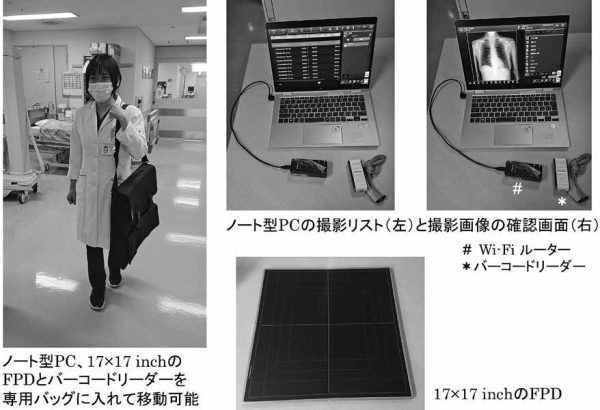

従来から使用していたX線ポータブル装置では、ワイヤレスFPDのみではDRシステムとして使用できない。そこで、RISからの患者情報と撮影メニューの取得、撮影をワイヤレスFPDで撮像、撮影後の画像処理や撮影した画像をPACSへ転送可能なノート型のpersonal computer(PC)を画像コンソールの役割として導入した(図5)。

このノート型PCを用いることで、X線ポータブル撮影をワイヤレスFPDで撮影した画像は、Wi-Fiを介して通信可能である。ノート型PCが14inchサイズと画面が小さいことやX線を曝射する際の操作が違う点以外は、DRシステム搭載のX線ポータブル装置と同様の撮影、画像処理と転送が行える。また、専用バッグに、ノート型PC、17×17inchのFPDとバーコードリーダーを入れて移動でき、感染エリアや手術室にある古いX線ポータブル装置もDRシステムとして使用可能と

なった(図6)。